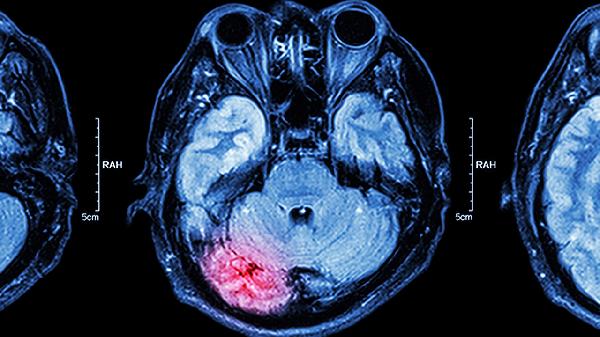

腦垂體腫瘤手術需注意術前評估、術中配合及術后護理,具體涉及內(nèi)分泌功能調(diào)整、感染預防、并發(fā)癥監(jiān)測等方面。手術方式主要有經(jīng)鼻蝶竇入路和開顱手術兩種,需根據(jù)腫瘤大小和位置選擇。

術前需完善內(nèi)分泌激素檢查,評估垂體功能狀態(tài)。對于功能性垂體瘤患者,可能需要使用溴隱亭片或醋酸奧曲肽注射液控制激素分泌異常。影像學檢查包括頭顱磁共振平掃加增強,明確腫瘤與周圍血管神經(jīng)的解剖關系。術前3天開始使用生理鹽水沖洗鼻腔,減少術后感染概率。合并高血壓或糖尿病患者需將血壓血糖控制在安全范圍。

術中采用神經(jīng)導航系統(tǒng)精確定位,避免損傷視交叉和頸內(nèi)動脈。對于向鞍上生長的腫瘤,需注意保護下丘腦結(jié)構。手術可能造成腦脊液漏,必要時需用闊筋膜或脂肪組織進行鞍底重建。麻醉過程中需監(jiān)測尿量變化,警惕尿崩癥發(fā)生。若出現(xiàn)難以控制的出血,可能需暫時中斷手術并輸血。